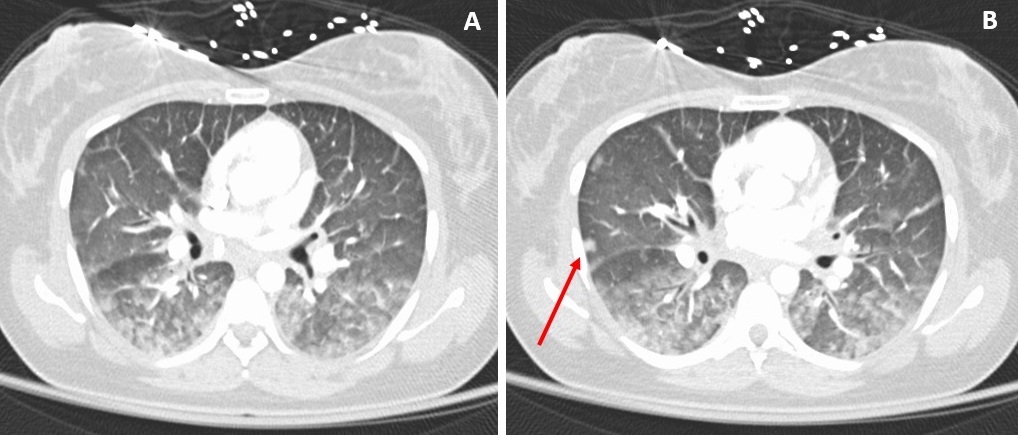

Results of an echocardiography scan confirmed global hypokinesis, indicative of myocarditis. The patient’s hypotension and tachypnea worsened. A computed tomography angiogram of the chest did not show a pulmonary embolism but was significant for extensive bilateral, posterior lung opacities with infiltrative processes involving the mediastinum, suggestive of possible pneumonia or mediastinitis with bilateral lung nodules (Figure 1).

Figure 1. A computed tomography scan showed extensive bilateral, posterior lung opacities with infiltrate process involving the mediastinum, suggestive of pneumonia (A). A 7-mm nodule was also noted in periphery of the right middle lobe (B).